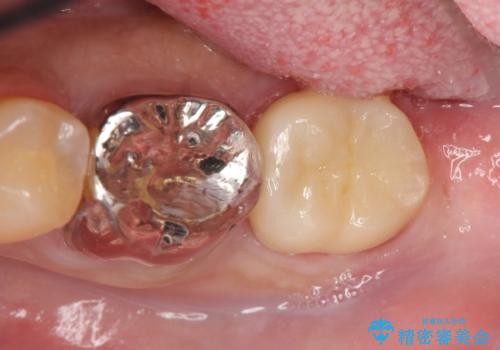

セラミックインレー 下の一番奥歯 歯ぐきの厚みを減らしてぴったりに入れます(ディスタルウェッジ+骨外科)